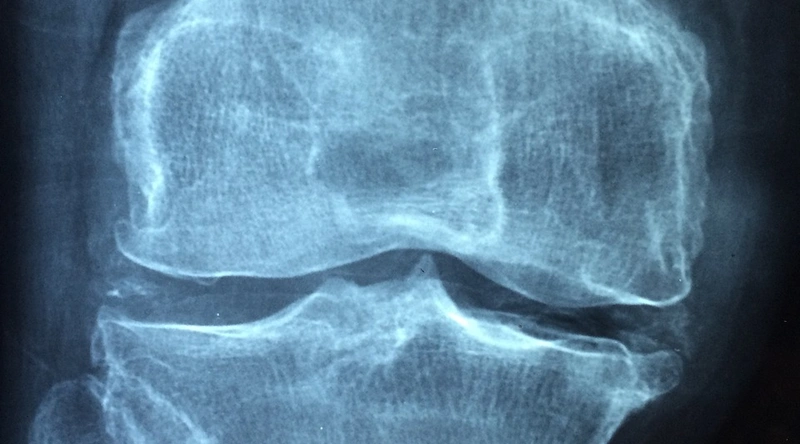

영상 검사

신체 검사가 끝난 후에는 X-레이, MRI와 같은 영상 검사가 필요할 수 있습니다. X-레이는 뼈의 상태를 확인하는 데 유용하며, MRI는 인대와 연조직의 손상을 확인하는 데 강력한 도구입니다. 진단 과정에서 필요한 검사를 종합적으로 고려하여 적절한 치료를 계획해야 합니다.

- X-레이: 뼈의 골절 유무 확인

- MRI: 연조직 손상 확인